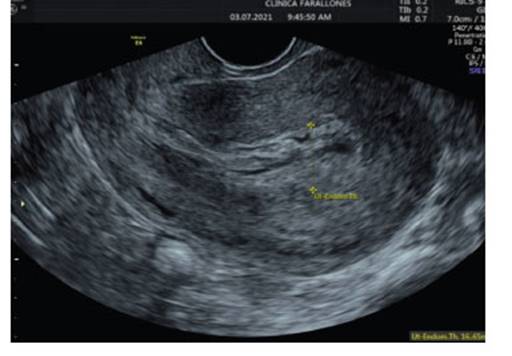

She consulted again 37 days later, due to abundant vaginal bleeding of sudden onset, associated with lipotimia. She was admitted to the emergency room. Transvaginal ultrasound was reported with RVF uterus, 82 x 55 x 56 mm, homogeneous endometrium of 9.2 mm without evidence of intrauterine gestation, greater than 4 weeks. Towards the fundus and posterior uterine region, a tortuous vascularized image at the level of the myometrium was identified with Doppler type II. Findings were suggestive of uterine vascular malformation (Figure 4).

Figure 4 homogeneous endometrium without evidence of intrauterine gestation, with size more than 4 weeks. towards the fundus and posterior region, a tortuous vascularized image was identified with doppler type ii.